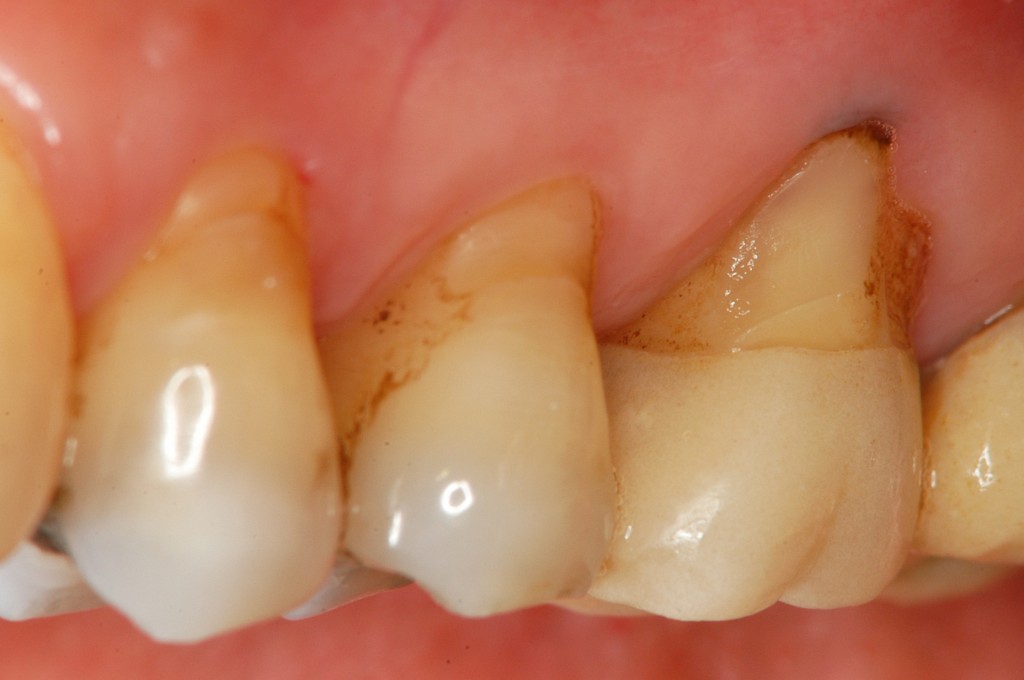

• 治療前

歯茎が下がってきた。歯茎がやせてきて気になる。歯周病かどうか心配。このままどんどん歯茎がやせてしまって,歯が抜けるのではないかと不安。

上の奥歯の歯茎がやせていて,根っこが見えている状態です。治療法はエムドゲインと結合組織移植を用いた根面被覆術を選択しました。

術前に比較して,露出していた根っこの面積が少なくなっているのがわかります。ご本人も大変喜ばれていました。